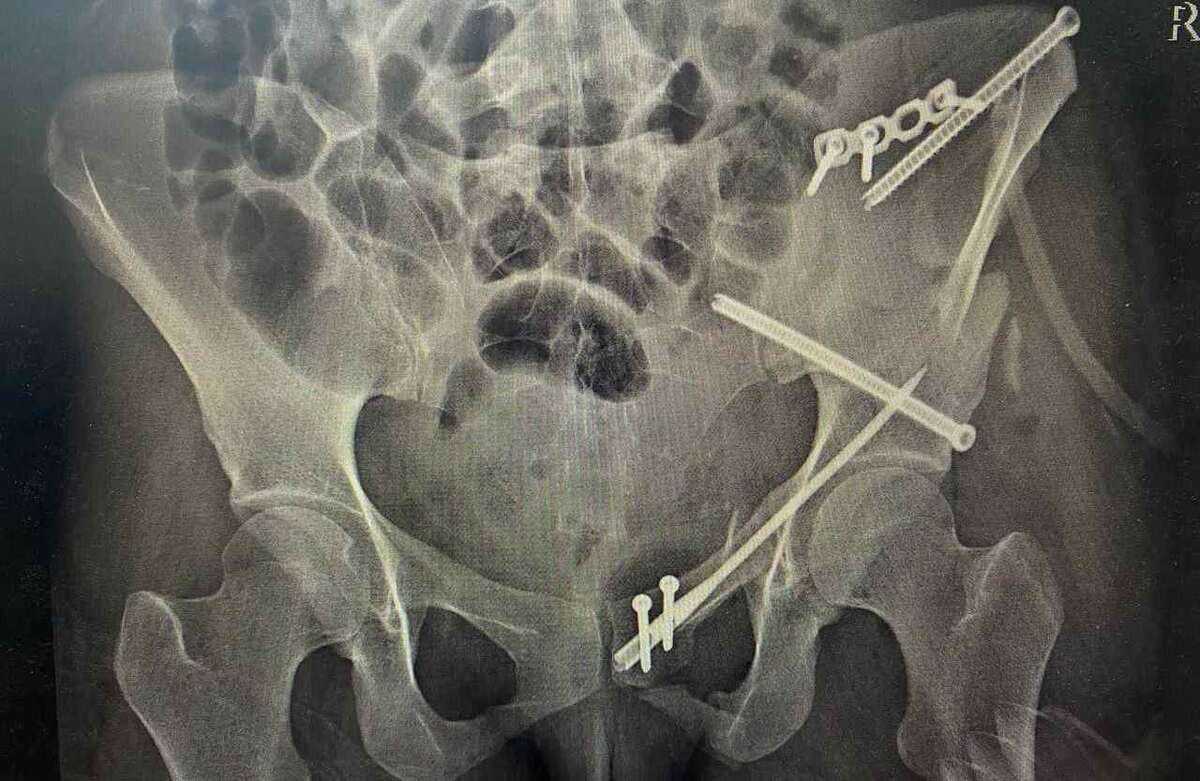

Пациентке после перелома провели сопоставление костей с устранением всех смещений и зафиксировали костные обломки винтами, блокируемым стержнем и титановой мини-пластиной.